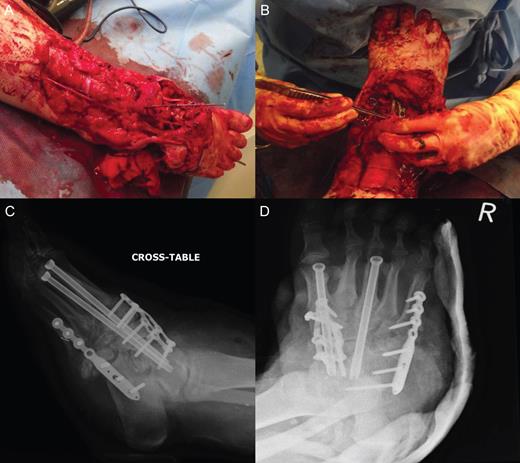

Wound debridement demonstrated pus at screw insertion sites with navicular and talar involvement. The patient had inadequate soft tissue coverage, bony osteomyelitis and necrotic bone. Primary limb shortening with a talectomy was conducted to reduce the soft tissue deficit and remove infected and necrotic bone, tibiocalcaneal arthrodesis for joint stability using external fixation, and dead space was treated with calcium sulphate mixed with vancomycin and systemic intravenous and oral antibiotics for osteomyelitis postoperatively (Figs 3 and 4). The wound was closed after the external fixator was applied. Wound swabs and bone samples revealed Enterococcus faecalis and E. raffinosus and diphtheroids. The patient was treated with intravenous teicoplanin and meropenem with oral stepdown to linezolid and ciprofloxacin.

Surgical images of talectomy and external fixation used for tibiocalcaneal arthrodesis. (A) Anterior posterior intraoperative radiograph illustrating talectomy. (B–D) Radiographs showing external fixation in situ.